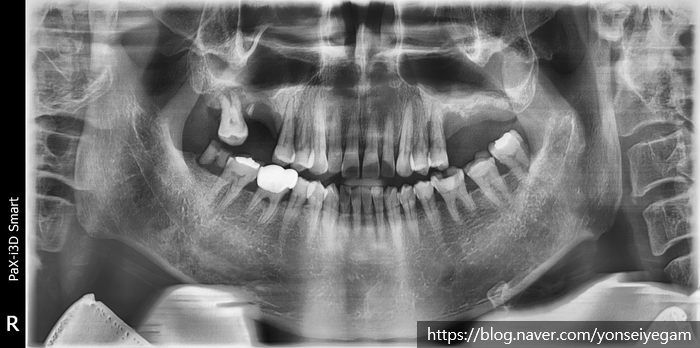

↑치료 전 사진입니다. 큰 어금니 쪽에 치아들이 성하지 않아

씹기가 힘든 상태입니다.